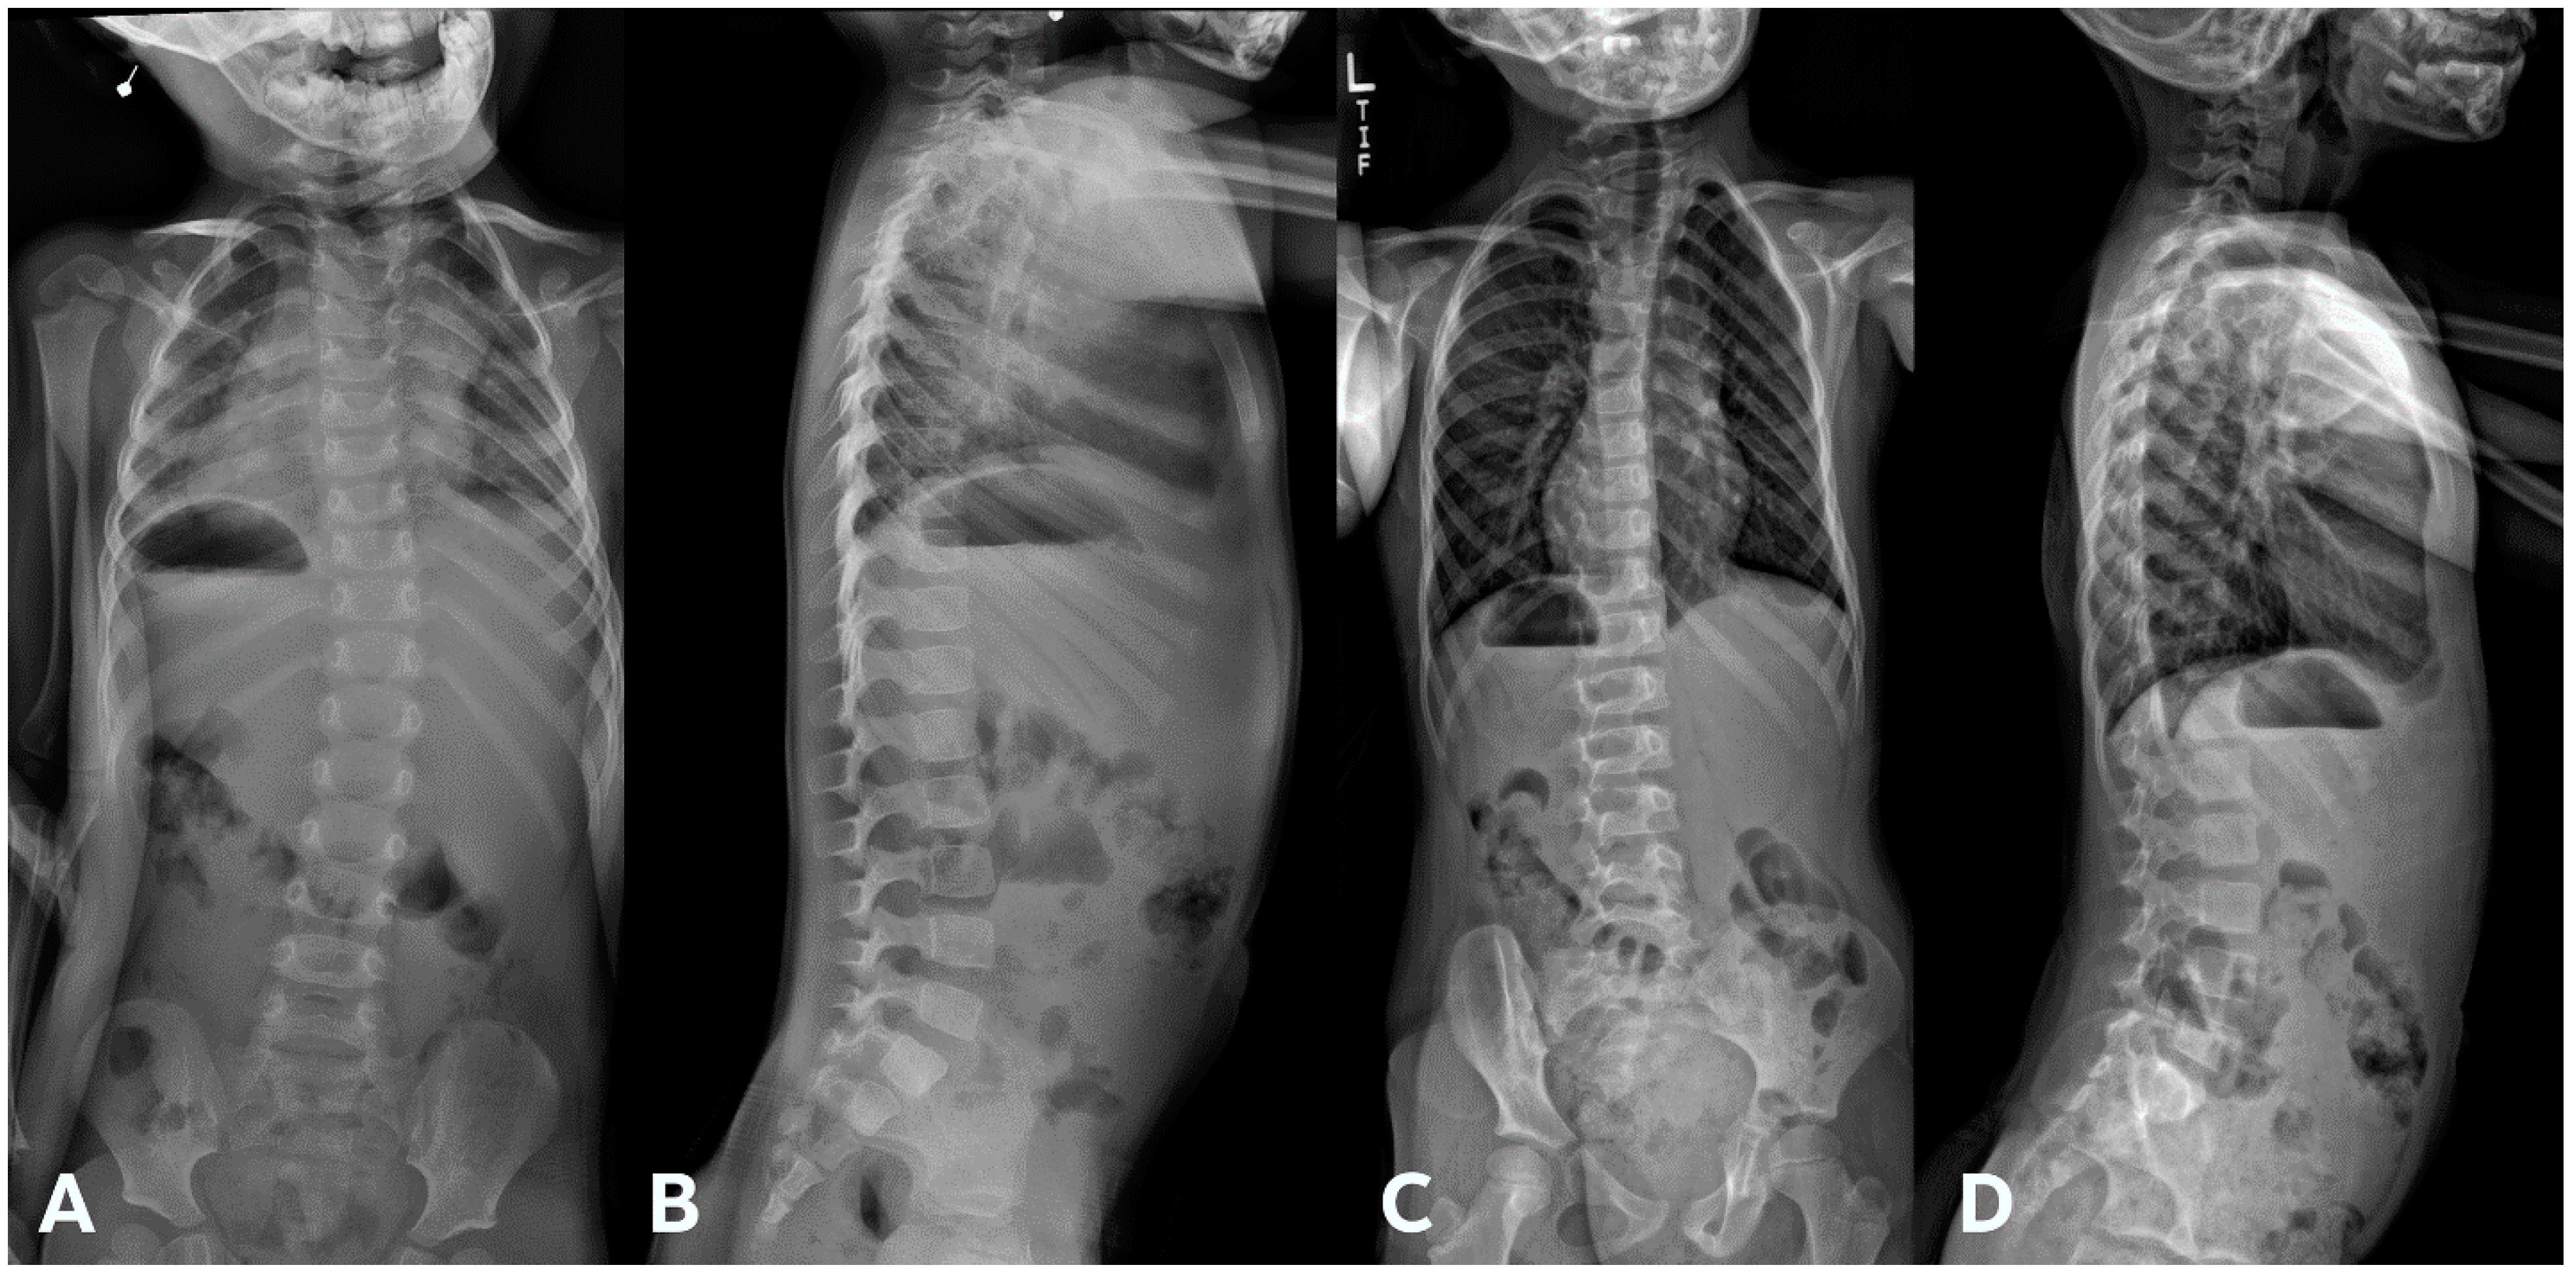

Figure 6.

(A,B) Initial PA and lateral radiograph of a 2-year-old child presenting with 17° of scoliosis at the cervicothoracic junction and T1 slope of 11°. (C,D) Follow-up radiographs showing a stable curve approximating 18° 4 years later.